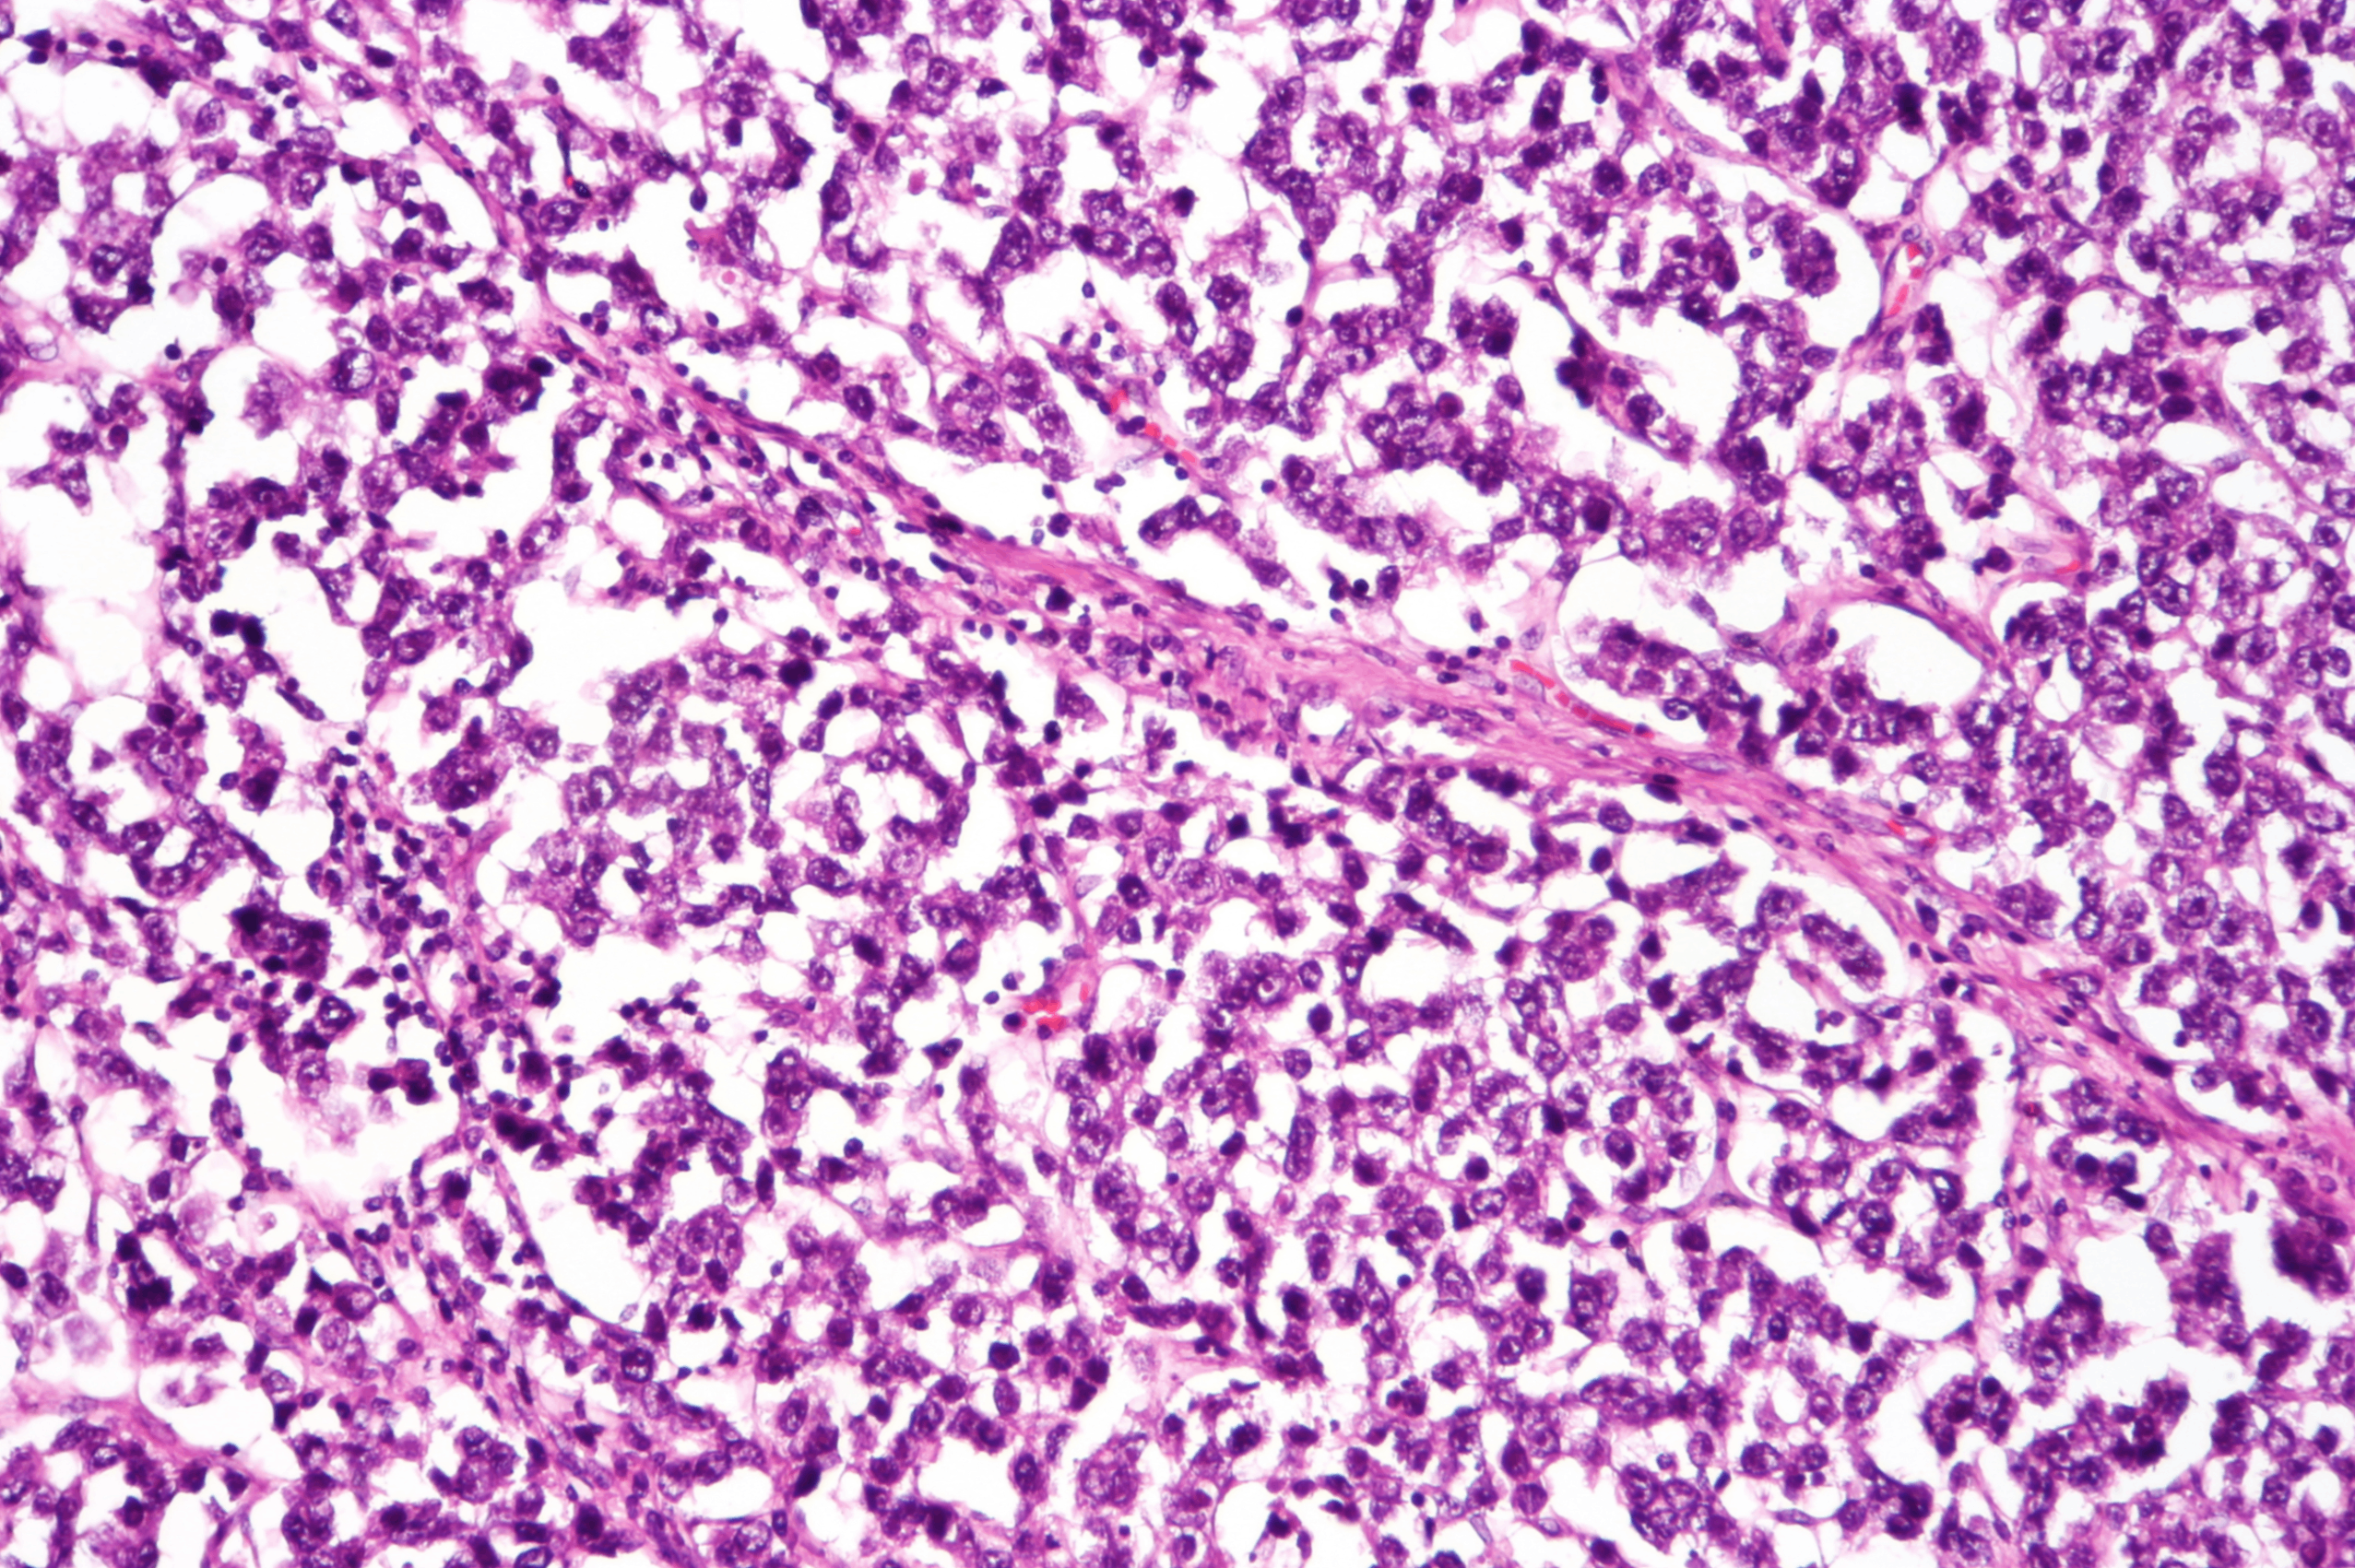

3) 조직학적 특징

• 연한 노란색/회백색의 일측성 종괴

다면형 세포, 크고 투명한 세포질, 세포간의 뚜렷한 경계, stroma에 침윤한 lymphocyte

OCT3/4, NANOG, KIT 발현

Dysgerminoma, Wikimedia Commons